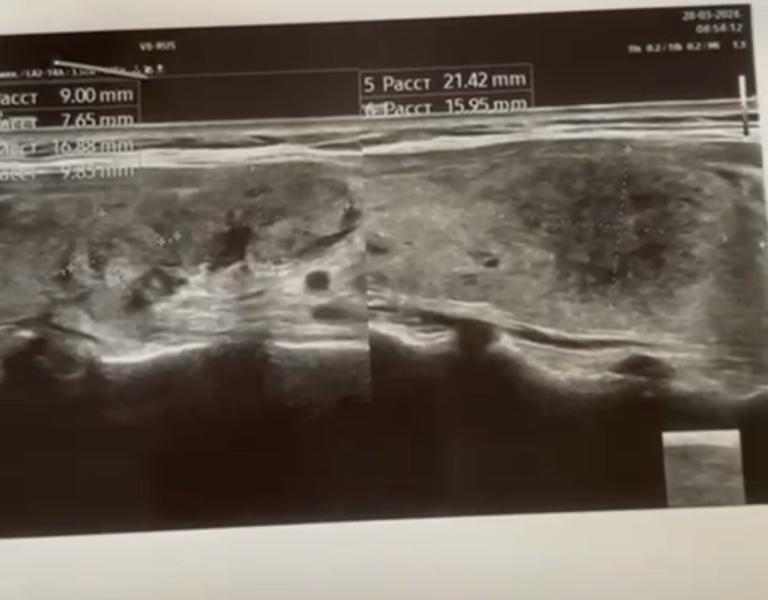

Сделала узи щитовидки, есть очаги. Была на приеме у эндокринолога тоже. В понедельник будет сдавать анализы. Пока будут результаты, я лопну от переживаний.